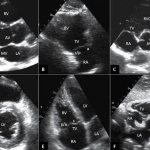

Diagnosis of angina pectoris during a painful attack The diagnosis of angina pectoris is often based on the following main signs: - the nature of the pain - compressive; - localization of pain - usually behind the sternum; - irradiation of pain - to the left shoulder girdle, to the lower jaw; - conditions of occurrence - physical stress, psycho-emotional arousal, exposure to cold; - the attack may be accompanied by tachycardia, moderate hypertension; - the temperature is normal; — clinical blood test is unchanged; - pain goes away after taking nitroglycerin or with rest. Primary assessment of the patient's condition The clinical diagnosis of angina is made on the basis of a detailed qualified survey of the patient, a thorough study of his complaints and a careful study of the anamnesis. All other research methods are used to confirm or exclude the diagnosis and clarify the severity of the disease - prognosis. Although in many cases the diagnosis can be made based on complaints, it should be borne in mind that the patient does not always accurately describe his feelings. Therefore, recently attempts have been made to create a so-called standardized questionnaire for patients suffering from angina (of course, its full use is possible in the interictal period). During the initial examination, before obtaining the results of an objective examination, it is necessary to carefully evaluate the patient’s complaints. Pain in the chest can be classified depending on the location, provoking and relieving factors: typical angina, probable (atypical) angina, cardialgia (non-coronary chest pain). With atypical angina, of the three main characteristics (all signs of pain, connection with physical activity, pain-relieving factors), two of them are present. With non-coronary chest pain, only one of the three characteristics occurs or they are absent altogether. For a correct diagnosis, the patient's habitus is important. When examining a patient during an attack of angina, a frightened facial expression, dilated pupils, perspiration on the forehead, somewhat rapid breathing, pale skin. The patient is restless and cannot lie still. There is an increase in heart rate and often an increase in blood pressure, and various heart rhythm disturbances are possible. In many patients, hypertension may have existed before the onset of angina, and an additional increase in blood pressure can only increase clinical symptoms. On auscultation, as a rule, tachycardia (rarely bradycardia) and muffled tones are noted.

Additional research methods for ischemic heart disease

Laboratory tests: - clinical blood test; - biochemical blood test: determination of total cholesterol, HDL cholesterol, LDL cholesterol, triglycerides, hemoglobin, glucose, AST, ALT in the blood. Instrumental diagnosis of myocardial ischemia: - recording ECG at rest; — ECG registration during an attack; — stress ECG tests (VEM, treadmill test); — EchoCG and stress echocardiography; — Holter 24-hour ECG monitoring (with MECG); — myocardial scintigraphy; — MRI; — KAG. Differential diagnosis with Cardiac neurosis Osteochondrosis Diaphragmatic hernia High gastric ulcer Angina pectoris must also be differentiated from syphilitic aortitis. Pain in the chest also occurs with other diseases, which should be remembered in case of atypical variants of coronary artery disease. Cardiovascular: - dissecting aortic aneurysm; - pericarditis; - pulmonary embolism. Pulmonary: - pleurisy; - pneumothorax; - lung cancer. Gastrointestinal: - esophagitis; - spasm of the esophagus; - reflux esophagitis; - intestinal colic. — Psychoneurological: — state of anxiety; - the heat of passion. Associated with the chest: - fibrositis; - injuries to the ribs and sternum; - intercostal neuralgia; - herpes zoster (before the rash stage). A separate category is reflex angina, which occurs due to pathology of nearby organs: peptic ulcer, cholecystitis, renal colic, etc. Prognosis of the course of coronary artery disease The quality and life expectancy of a patient with angina depends on: - early detection of the disease; — compliance with the regimen of taking prescribed medications; — lifestyle changes and elimination of risk factors. In other words, if you make certain changes in your lifestyle and take recommended medications, you can continue to live a full life. The main conditions for this are an understanding of the essence of the condition and the patient’s willingness to cooperate with medical personnel. Treatment and treatment goals : - improve the prognosis and prevent the occurrence of myocardial infarction or SCD and accordingly increase life expectancy; - reduce the frequency and intensity of angina attacks in order to improve the quality of life. The choice of treatment method depends on the response to initial drug therapy, although some patients immediately prefer and insist on surgical treatment - TKA, CABG. In the selection process, the patient’s opinion is taken into account, as well as the ratio of price and effectiveness of the proposed treatment. Non-drug treatment of angina pectoris includes: lifestyle changes and counteracting risk factors for coronary artery disease. Drug treatment of angina pectoris 1. Antianginal (anti-ischemic) therapy This treatment is prescribed to patients with attacks of angina or when diagnosing episodes of myocardial ischemia using instrumental methods. Antianginal drugs include: - beta blockers; - calcium antagonists; - nitrates; - nitrate-like drugs; — myocardial cytoprotectors. It is recommended that these classes of drugs be prescribed in this order for the treatment of stable angina, and that they be used in various combinations. Drugs that are not recommended to be prescribed to patients for the treatment of angina pectoris: vitamins and antioxidants, female sex hormones, riboxin, adenosine triphosphate (ATP), cocarboxylase. 2. Medicines that improve the prognosis in patients with angina pectoris. They are recommended for all patients diagnosed with angina pectoris in the absence of contraindications. Antiplatelet drugs, more correctly called antiplatelet agents (acetylsalicylic acid - ASA, clopidogrel) are mandatory treatments for stable angina. All patients after myocardial infarction are recommended to be prescribed a BB without internal sympathomimetic activity: metoprolol, bisoprolol, propranolol, atenolol. Lipid-lowering drugs Beta-blockers (selective action) - Metoprolol (betaloc ZOK, Corvitol, Egilok, Emzok) 50-200 mg 2 times a day. — Atenolol (atenolan, tenormin) 50-200 mg 1-2 times a day. — Bisoprolol (bisogamma, concor, concor cor) 10 mg/day. — Betaxolol (betak) 10-20 mg/day. — Pindolol (Wisken) 2.5-7.5 mg 3 times a day. — Nebivolol (nebilet) 2.5-5 mg/day. - Carvedilol (acridilol, Dilatrend, Cardivas) - 25-50 mg 2 times a day. Calcium antagonists 1. Dihydropyridine - Nifedipine - moderately prolonged (adalat SL, cordaflex retard, corinfar retard) 30-100 mg/day; significantly prolonged (osmo-adalat, cordipin CL, nifecard CL) 30-120 mg/day. — Amlodipine (norvasc, cardlopin, normodipine, kalchek, amlovas, vero-amlodipine) 5-10 mg/day. — Felodipine 5-10 mg/day. — Isradipine 2.5-10 mg 2 times a day. — Lacidipine 2-4 mg/day. 2. Non-dihydropyridine - Diltiazem (diltiazem-Teva, diltiazem Lannacher) 120-320 mg/day. - Verapamil (isoptin, lecoptine, finoptin) - 120-480 mg/day. Nitrates and nitrate-like drugs 1. Nitroglycerin preparations - Short-acting (nitromint, nitrocor, nitrospray) 0.3-1.5 mg sublingually for angina pectoris. — Long-acting (nitrong forte) 6.5-13 mg 2-4 times a day. 2. Preparations of isosorbide dinitrate - Long-term action (cardiquet 40, carditet 60, carditet 120, iso Mac retard) 40-120 mg/day. — Moderate duration of action (isolong, cardiket 20, iso Mak 20, nitrosorbide) 20-80 mg/day. 3. Preparations of isosorbide mononitrate - Moderate action (monosan, monocinque) 40-120 mg/day. - Long-acting (olicard retard, monocinque retard, pectrol, efox long) 40-240 mg/day. 4. Molsidomine preparations - Short-acting (Corvaton, Sidnopharm) 4-12 mg/day. — Moderate duration of action (dilasid) 2-4 mg 2-3 times a day. — Long-acting (dilasidom retard) 8 mg 1-2 times a day. Surgical treatment of coronary artery disease The main indication for surgical treatment of coronary artery disease is the persistence of severe angina (FC III-IV), despite intensive drug treatment. The indications and nature of surgical treatment are specified based on the results of coronary angiography and depend on the degree, prevalence and characteristics of coronary artery lesions. Patients with frequent attacks of angina pectoris and insufficient drug therapy or those with multiple risk factors, including a family history of sudden death, should undergo angiographic examination of the coronary arteries. If narrowing of the main left trunk of the coronary artery and changes in 3 coronary arteries are detected, myocardial revascularization is indicated. Myocardial revascularization includes - Various types of TKA (transcutaneous angioplasty) with the installation of a metal frame - an endoprosthesis (stent), burning out the plaque with a laser, destroying the plaque with a rapidly rotating drill and cutting off the plaque with a special atherotomy catheter. — CABG surgery to create an anastomosis between the aorta and the coronary artery below the site of narrowing to restore effective blood supply to the myocardium. Currently, there is a definite tendency to bypass the maximum possible number of coronary arteries using autoarteries. For this purpose, the internal mammary arteries, radial arteries, right gastroepiploic and inferior epigastric arteries are used. Vein grafts are also used. Despite the quite satisfactory results of CABG, angina returns in 20-25% of patients within 8-10 years. Such patients are considered candidates for reoperation. More often, the return of angina is caused by the progression of coronary atherosclerosis and damage to autovenous shunts, which leads to stenosis and obliteration of their lumen. Shunts are especially susceptible to this process in patients with risk factors: hypertension, diabetes mellitus, dyslipidemia (DLD), smoking, obesity. Medical examination of patients with coronary heart disease Patients with coronary artery disease and various types of angina are subject to medical examination in cardiology centers or cardiology clinics for life.